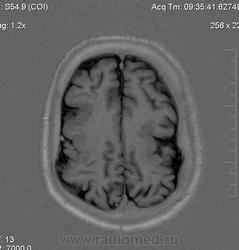

Мужчина 32 лет. Из анамнеза: перинатальное повреждение ЦНС, ДЦП, дизартрия, правосторонний верхний монопарез. С 16 лет приступы эпилепсии.

Аплазия прозрачной перегородки. Шизэнцефалия с открытыми краями в лобно-теменной области слева. Шизэнцефалия с закрытыми краями в лобной области справа? Утолщение коры по контуру расщелин и в области глазничной извилины правой лобной доли. Микрогирия? Гиперостоз костей свода черепа. Уважаемые коллеги, возможно я ошибаюсь, или есть еще аномалия?

На мой взгляд, полимикрогирия двусторонняя (конвекситальные отделы дорзальных отделов лобных долей и частично теменных, а также в базальном отделе полюса правой лобной доли) + закрытая шизенцефалия левой лобно-теменной области. Аплазия прозрачной перегородки (как признаки лобарной голопрозенцефалии).